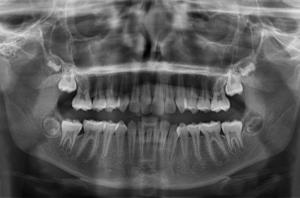

• Des radiographies : Panoramique (pour une vision d’ensemble de la denture et de l’évolution dentaire), de profil (pour voir les relations et décalages entre les mâchoires) et si nécessaire du poignet (pour estimer le stade de croissance du patient et la croissance résiduelle disponible) et de face (pour mettre en évidence des asymétries)

• Des empreintes dentaires pour obtenir des moulages d’étude

À partir des éléments de ce bilan orthodontique, le praticien va pouvoir analyser les données cliniques, les photos, les radiographies pour une analyse céphalométrique et les moulages pour établir un diagnostic précis et proposer un traitement adapté.